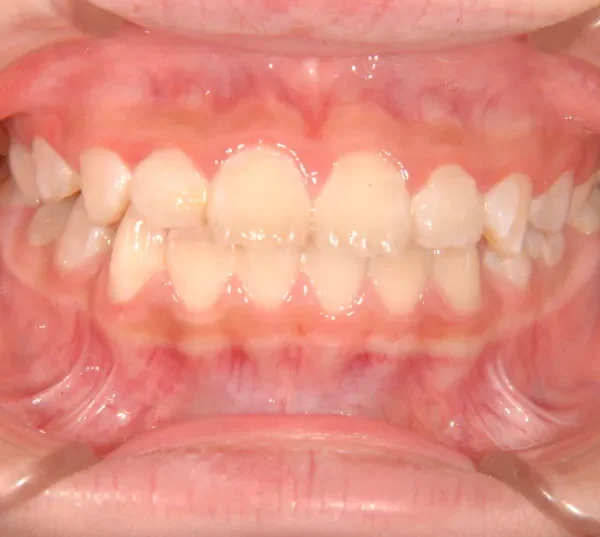

【子供の矯正(一期)】叢生・反対咬合・受け口・非抜歯症例・7歳女児【M.H様】

初診時年齢 小学校1年生 (女性) 主訴 受け口

診断名 叢生・反対咬合 装置名

状態 永久歯が生える隙間がない(叢生)

受け口(下顎前突/反対咬合)

下顎が大きい傾向があります。

上下の真ん中にズレがあるのと、上下とも永久歯の生えるスペースがせまいため、オリジナル矯正装置でスペースを作り、受け口も改善していきます。

治療回数21回、2年7ヶ月の治療期間で矯正治療を終了しました。

主訴が改善され、ご満足頂きました。

初診

治療終了後